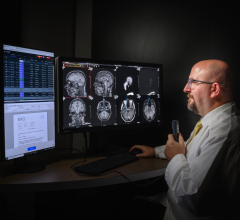

The NovaMG breast imaging viewer combines the tool set of NovaPACS with customizable mammographic reading and hanging protocol sequences. FDA 510(k) cleared and IHE compliant, it supports multi-modality viewing and iCad and R2 structured reports.

The viewer enables direct receipt of digital mammographic images from the modality while pre-fetching from the PACS archive is initiated via DICOM modality worklist.

Offered as an option to NovaRad’s existing radiologist view stations, the viewer provides all pixels viewing that allows for searching of all image pixels and incorporates Tabár’s systematic viewing masks to enhance perception of subtle radiographic abnormalities. All annotations and additions to image information such as Grayscale Softcopy Presentation State (GSPS), queried and retrieved images and structured reports are stored in the PACS upon completion of interpretation.

NovaMG automatically populates the diagnostic findings to a mammography reporting system and facilitates work list synchronization for recall-report exporting from either the RIS or mammography reporting system.

In addition to NovaMG, NovaRad offers NovaPACS, NovaRIS, NovaPro for radiologist groups, NovaCardio PACS, and ClinicPACS orthopedic PACS radiology technologies. Its systems are used by more than 450 facilities around the globe.